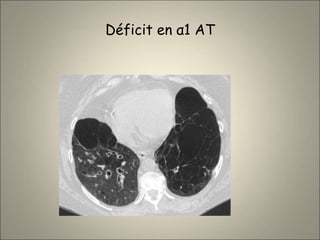

• Déficit en α1 anti trypsine : EPL avec bronchectasies

Déficit en α1 AT